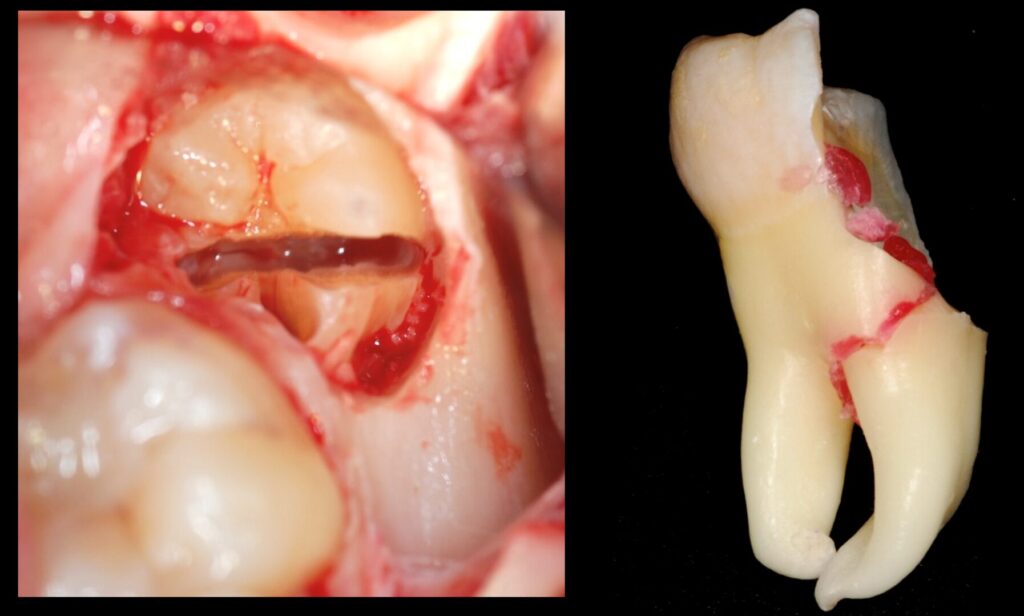

• TECNICHE DI OSTEOTOMIE E ODONTOTOMIE -RIZOTOMIA E REVISIONE DELLA CAVITÀ

CORSISTI DI ESTRAZIONI COMPLESSE DI III° MOLARI